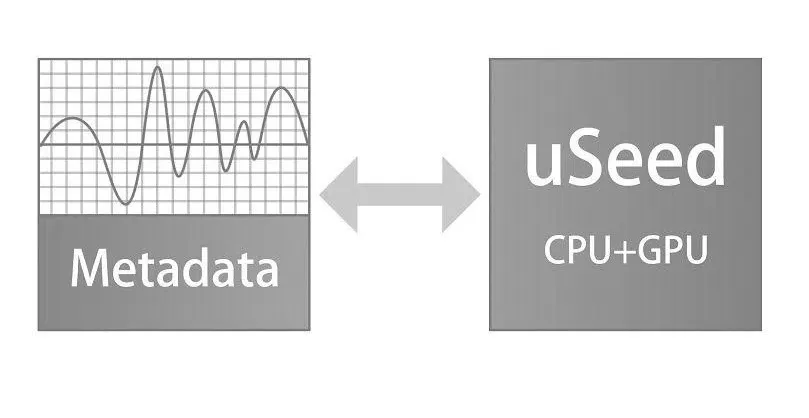

uSeed

Изображения в платформе uSeed сохраняются в виде метаданных для последующей обработки с использованием технологии параллельных вычислений CPU + GPU. Многократно повышена производительность системы и частота кадров при формировании изображений

- uSeed